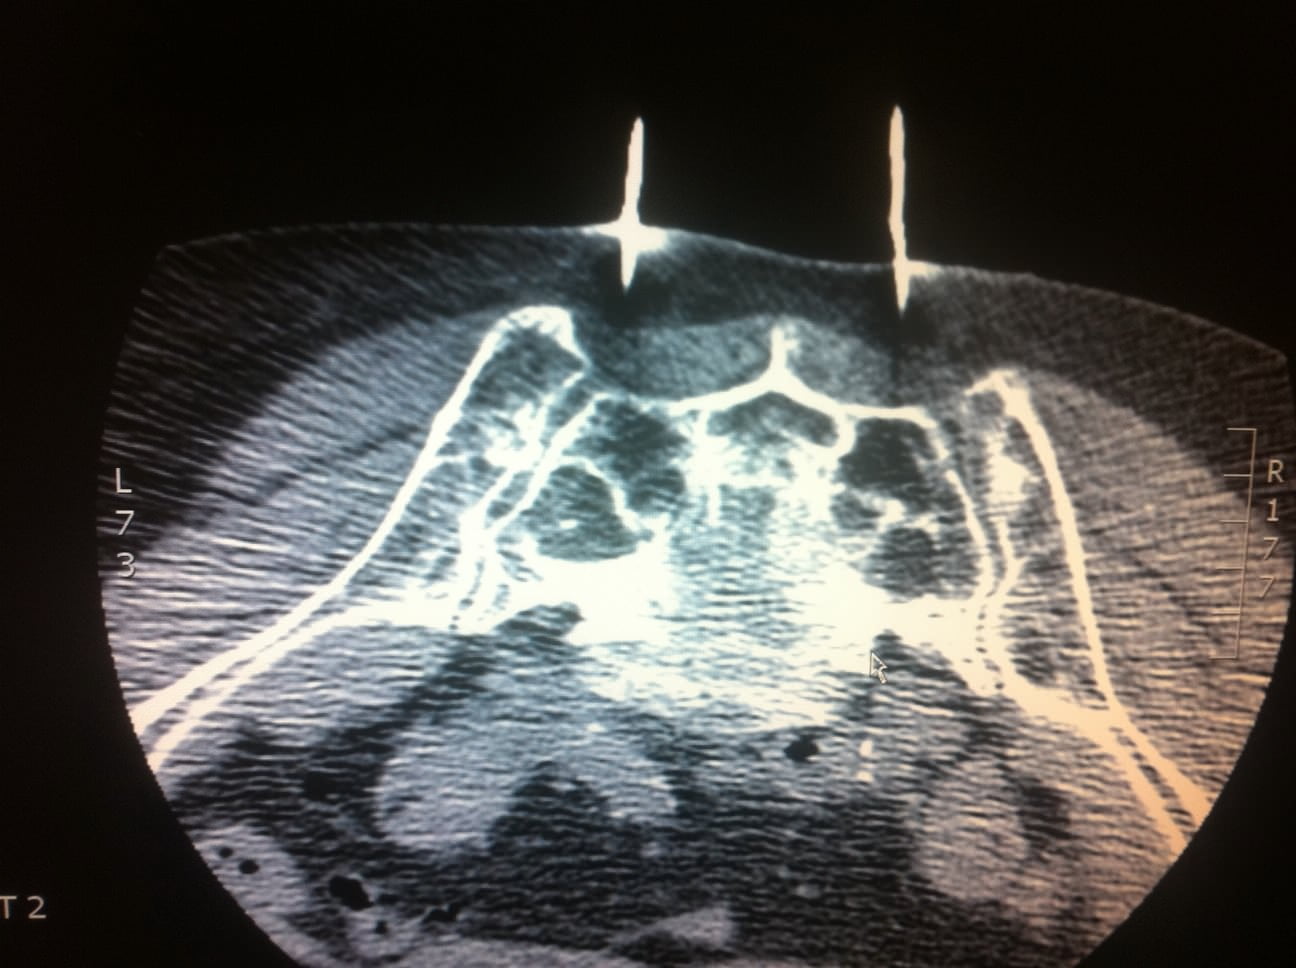

Bilateral sacral fractures (in line with arrows) are clearly visualized

Bilateral sacral fractures (in line with arrows) are clearly visualized Sacrum Fracture Running They have been described in a few case reports, with the injury occurring most. Imaging with ct or mr is pathognomonic. Unlike muscle or tendon pains that might loosen or ease when you move, pain from a sacral fracture usually intensifies during a run, lingers afterward, and progressively worsens over time until. Sacral fractures are often missed or misdiagnosed by. Sacrum Fracture Running.